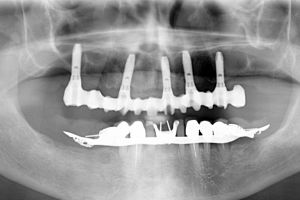

Operando in sedazione cosciente, abbiamo estratto i denti compromessi e inserito immediatamente 5 impianti dentali. Nel giro di 24 ore, Marco ha ricevuto i suoi denti provvisori fissi.

L’uso del software ci ha permesso di sfruttare l’osso naturale residuo del paziente, che è sempre il materiale migliore su cui lavorare. In questo modo abbiamo potuto applicare il protocollo del carico immediato, offrendo a Marco denti fissi in pochissimo tempo, un risultato impossibile da raggiungere se avessimo dovuto fare innesti ossei complessi.

Gli impianti sono stati posizionati in punti strategici per ottenere due risultati fondamentali: far uscire i denti direttamente dalla gengiva naturale di Marco e chiudere gli spazi antiestetici che si erano creati a causa della malattia.